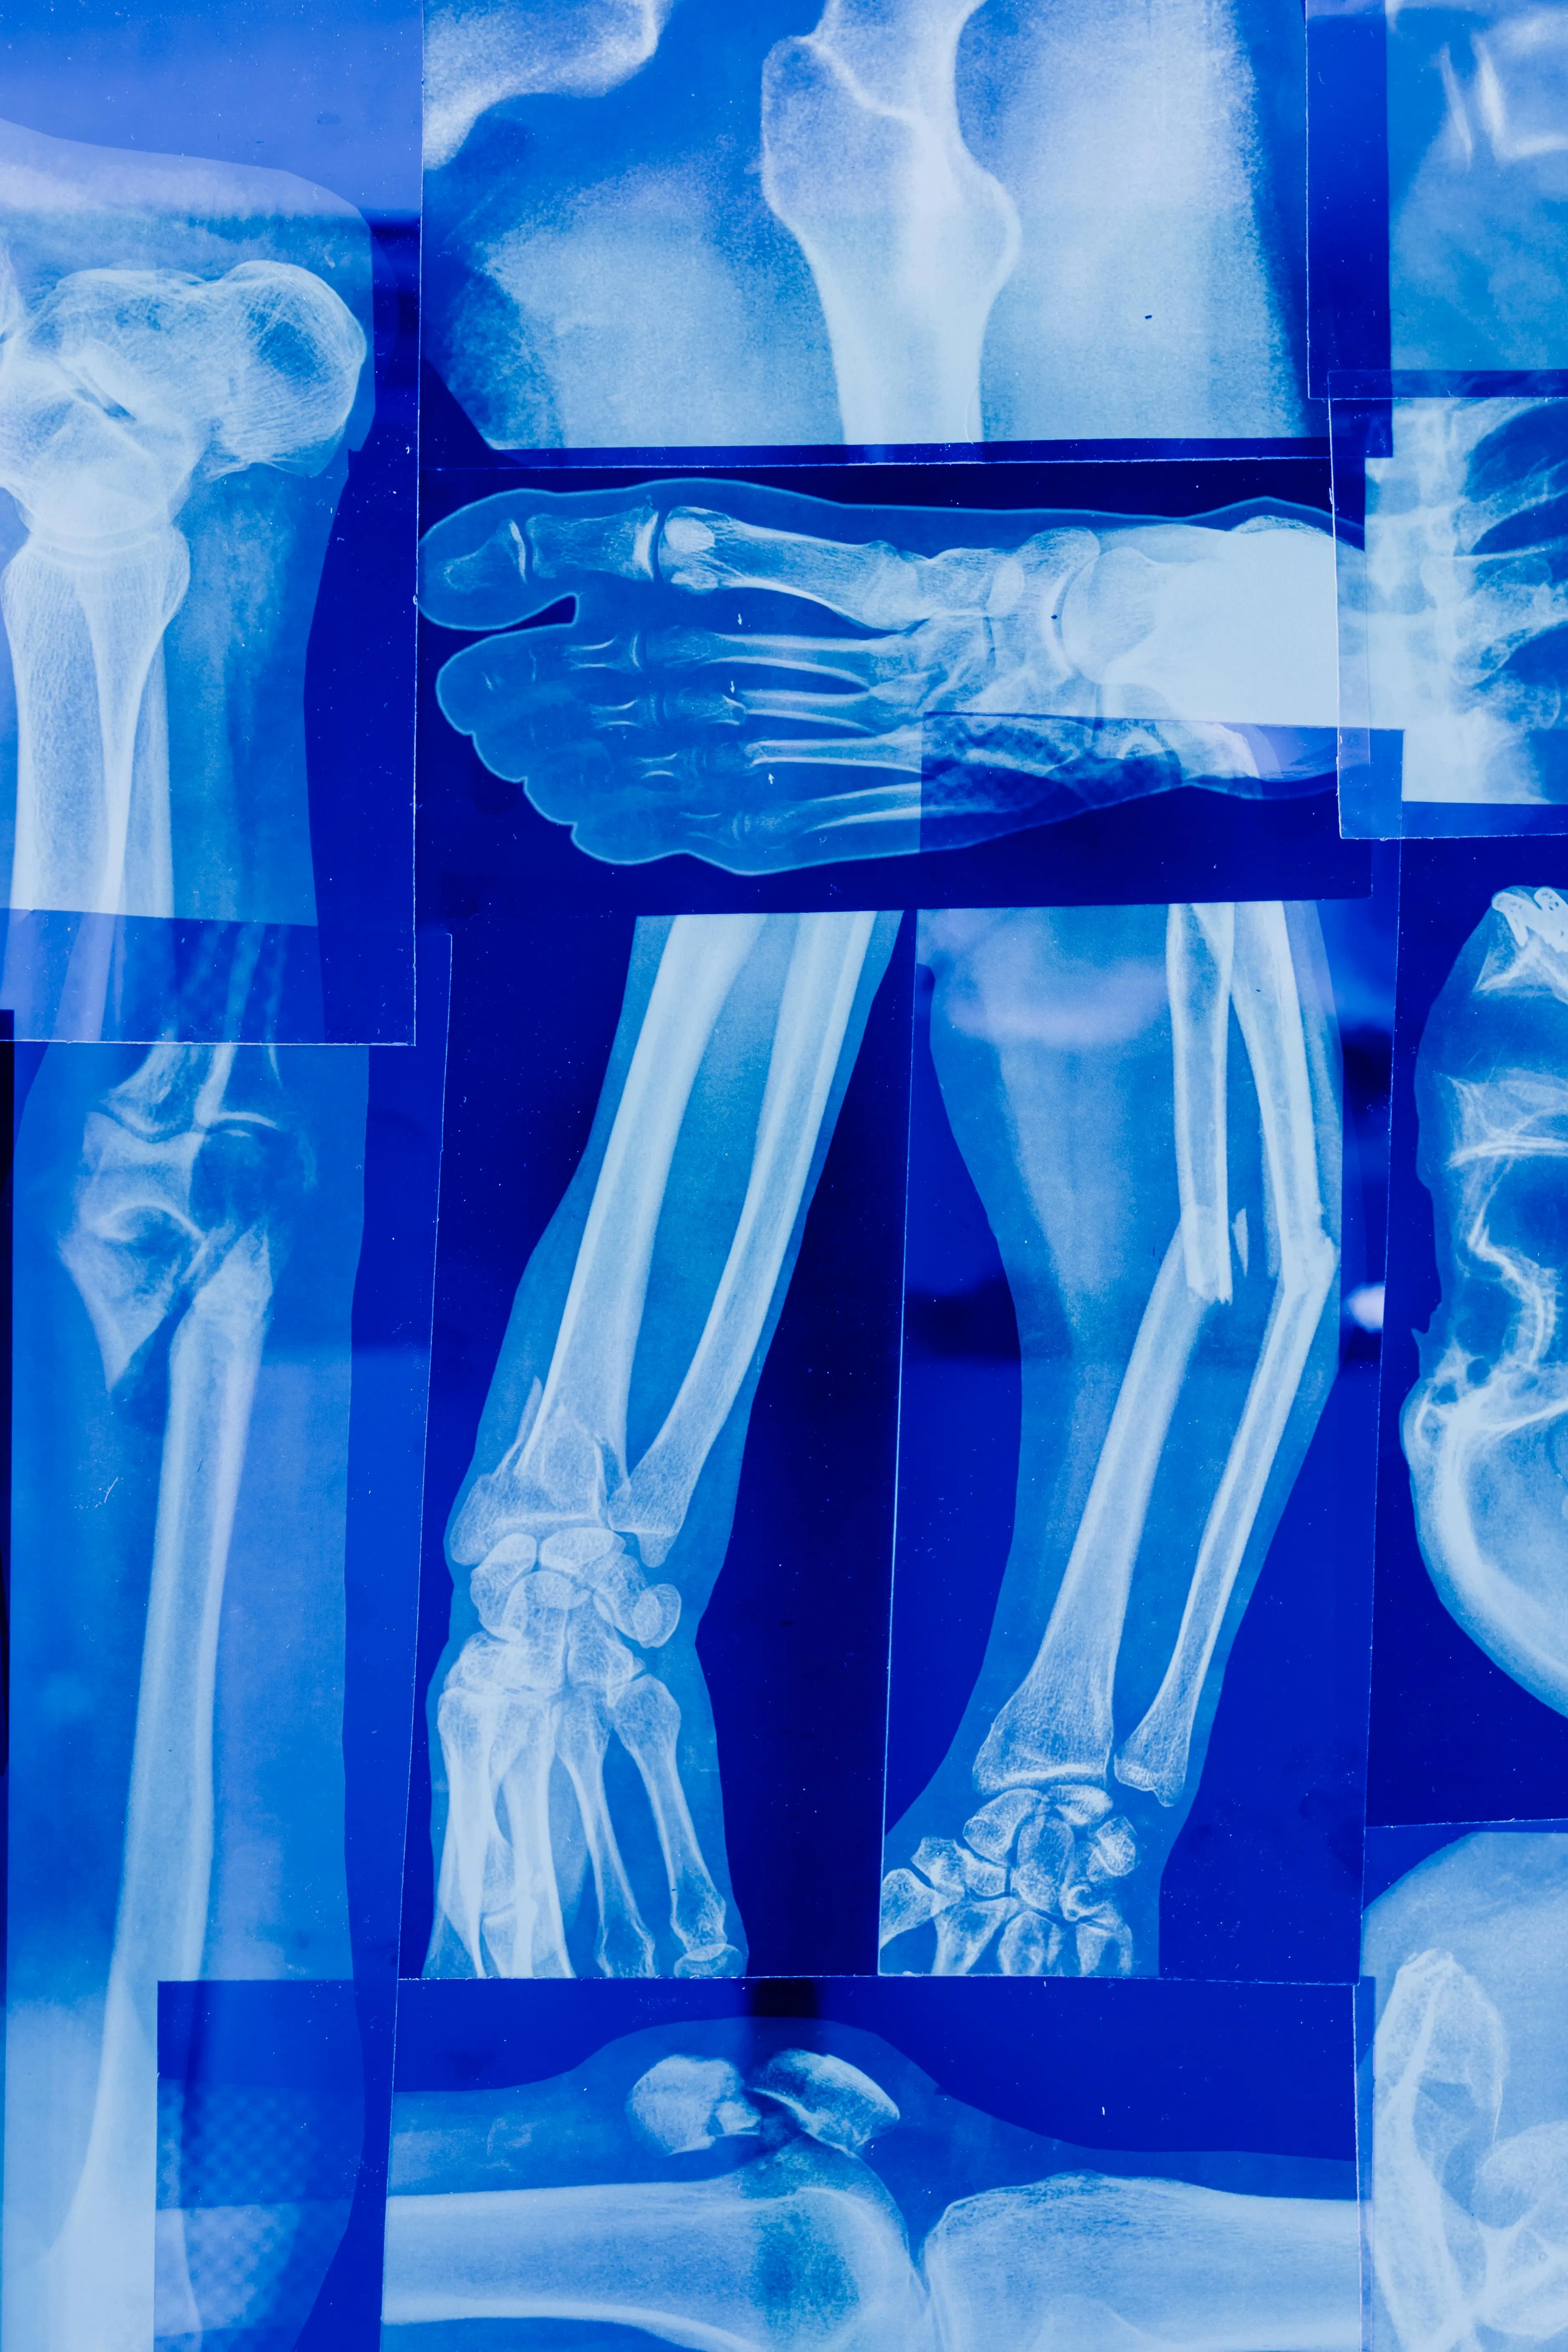

콘드로이친(Chondroitin)은 우리 몸의 연골과 결합조직 속에 자연적으로 존재하는 성분으로

관절 사이에서 충격을 흡수하고 마찰을 줄여주는 역할을 합니다.

나이가 들면서 콘드로이친이 점점 감소하면 관절이 뻣뻣해지고 통증이 생길 수 있다고 합니다.

콘드로이친은 연골 보호, 관절 윤활, 통증 완화, 피부 탄력 개선 등

여러 방면에서 건강에 도움을 주는 영양소라고 합니다.